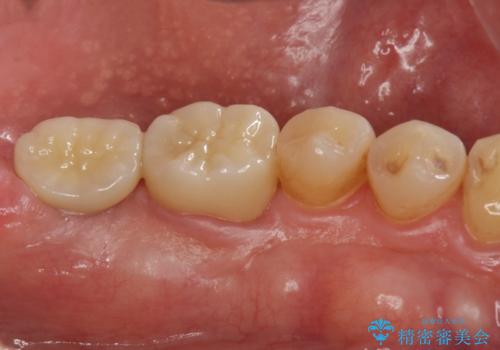

インプラント治療・セラミック治療を含む 全顎的虫歯治療

以上のような問題を、徹底的な虫歯治療、歯周外科、インプラント治療、部分矯正治療、精密根管治療を用いてひとつずつ解決ししっかりと長期的に食事を楽しめるような口腔内環境の再構築を目指します。